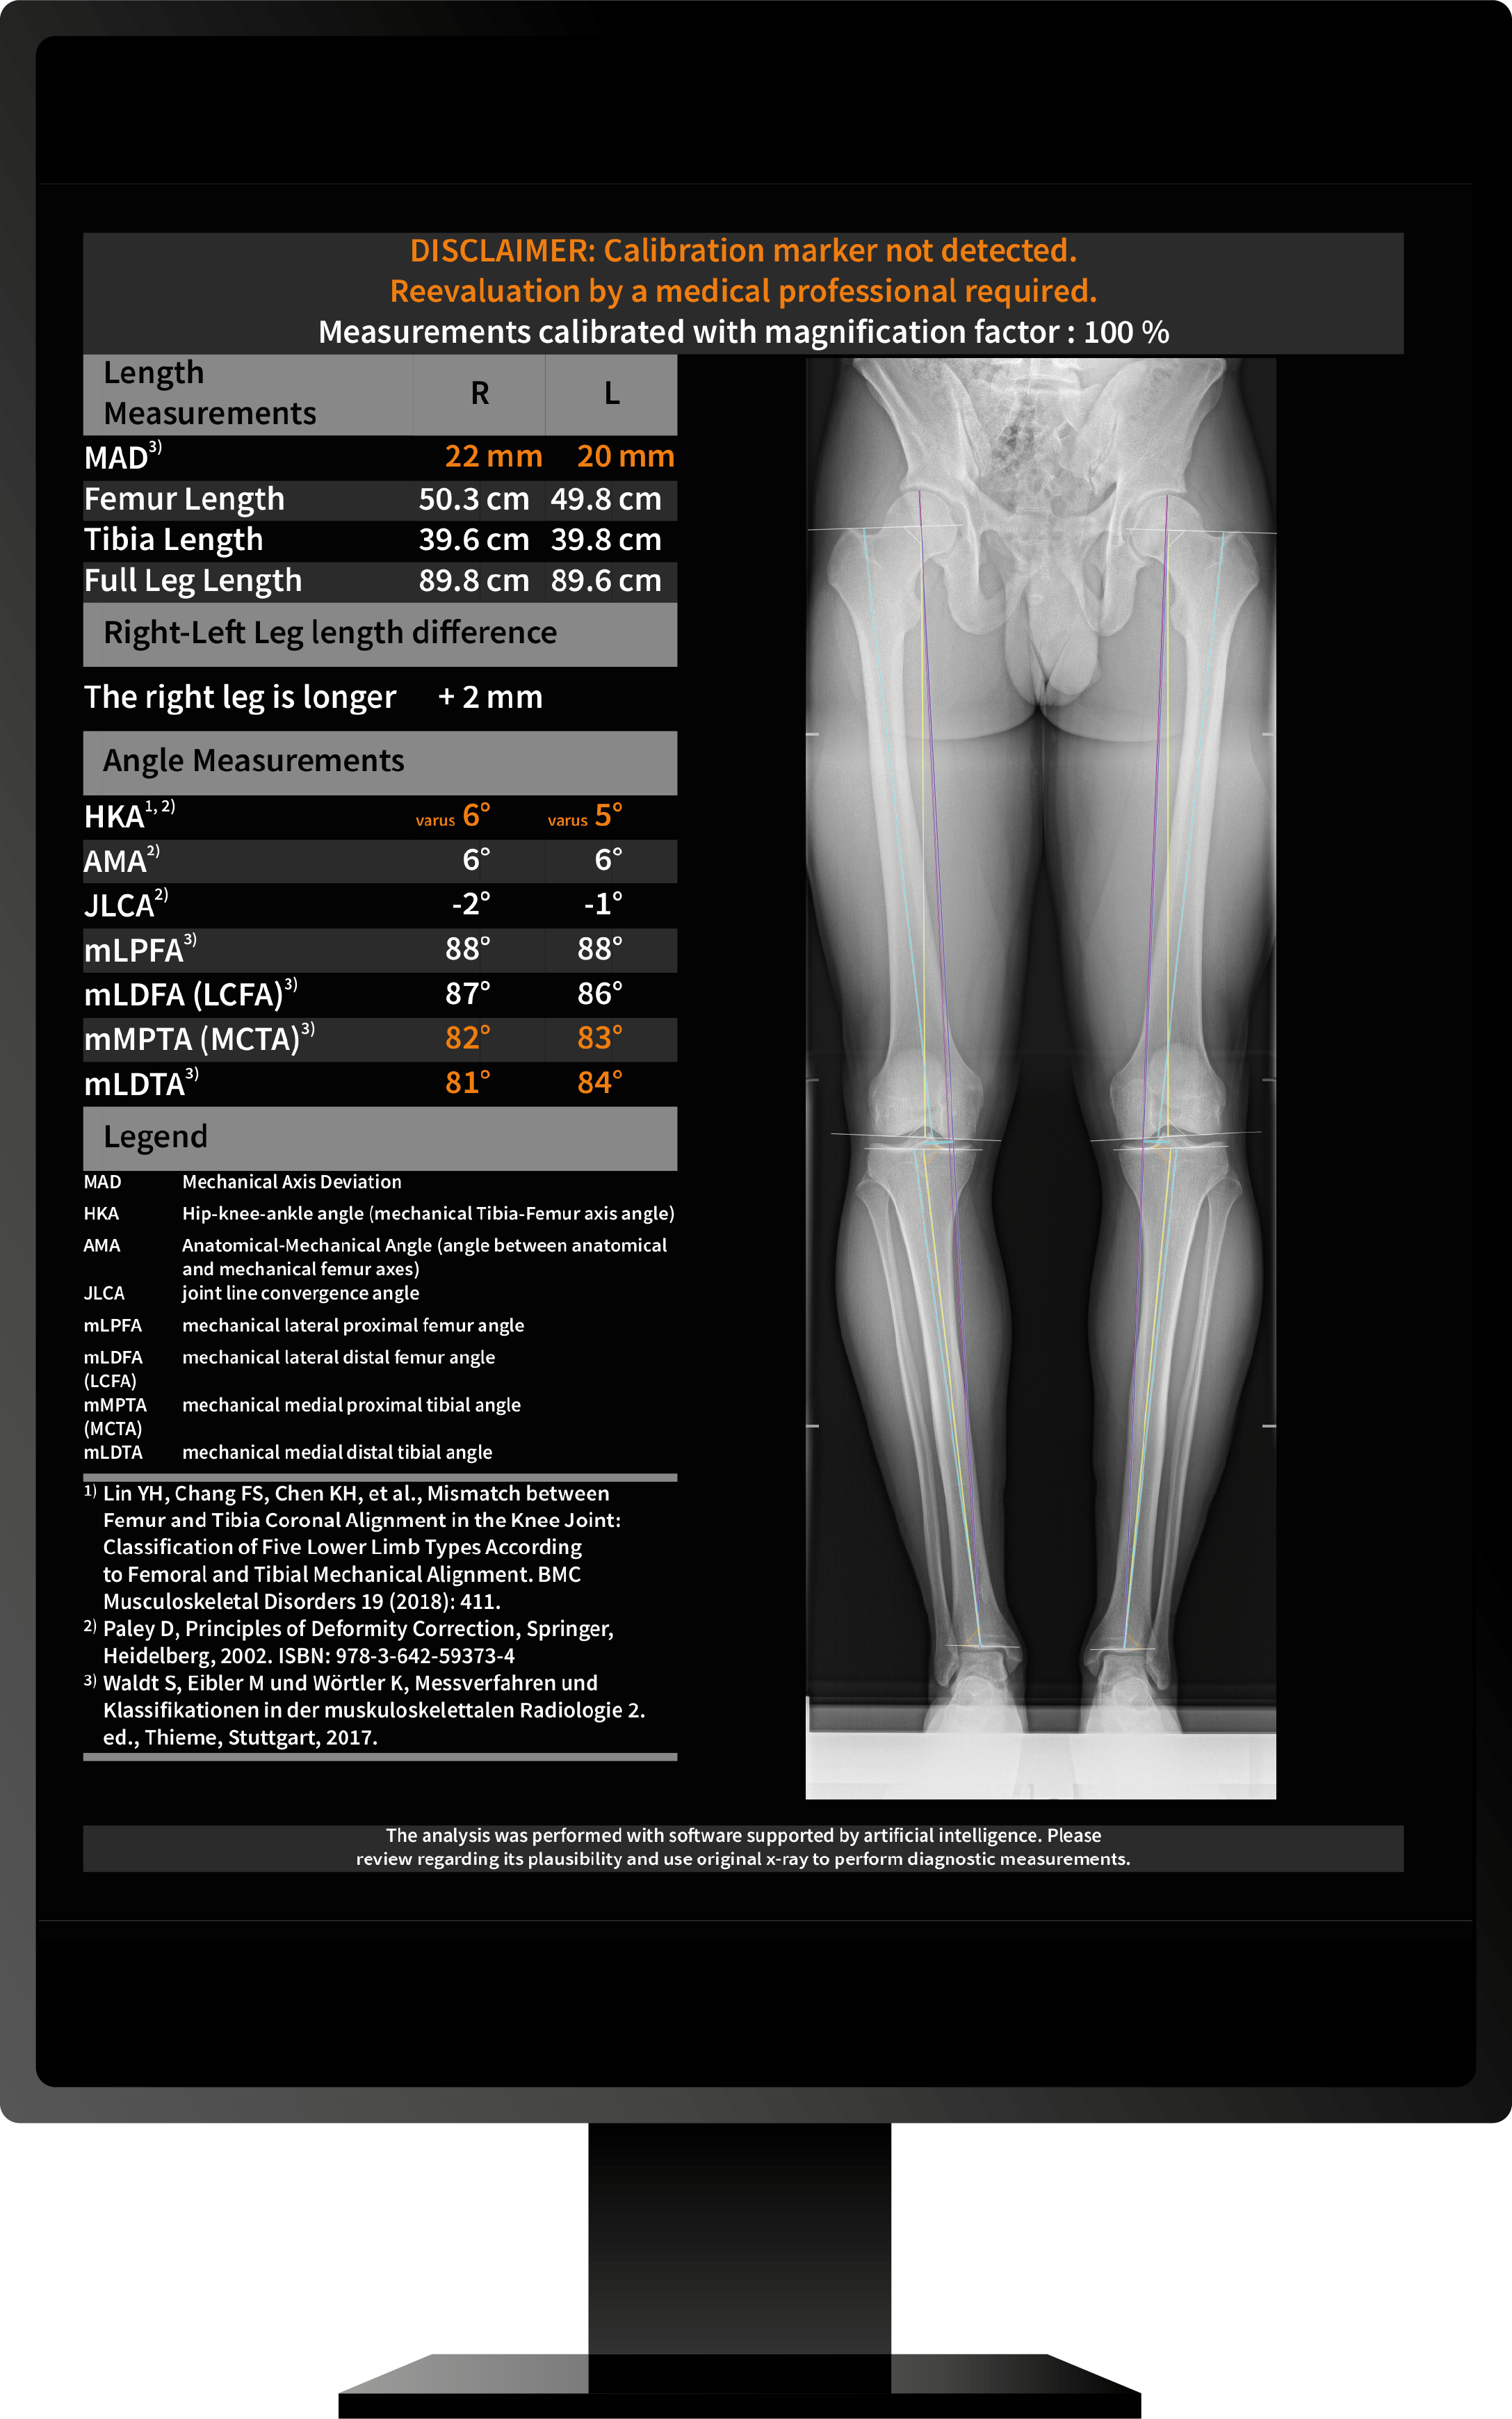

IB Lab LAMA is one of four MSK modules that provide diagnostic support for the most common bone and joint diseases in medical practices and clinics. The application was developed for MSK-radiologists and orthopedic surgeons, providing up to twelve measurements on long-leg X-rays with or without hip or knee implants. IB Lab LAMA automatically locates the anatomical features of the femur, tibia, and calibration ball to provide all the landmarks needed for the required measurements. If a calibration ball is available, IB Lab LAMA uses a corresponding magnification factor for the length measurement.